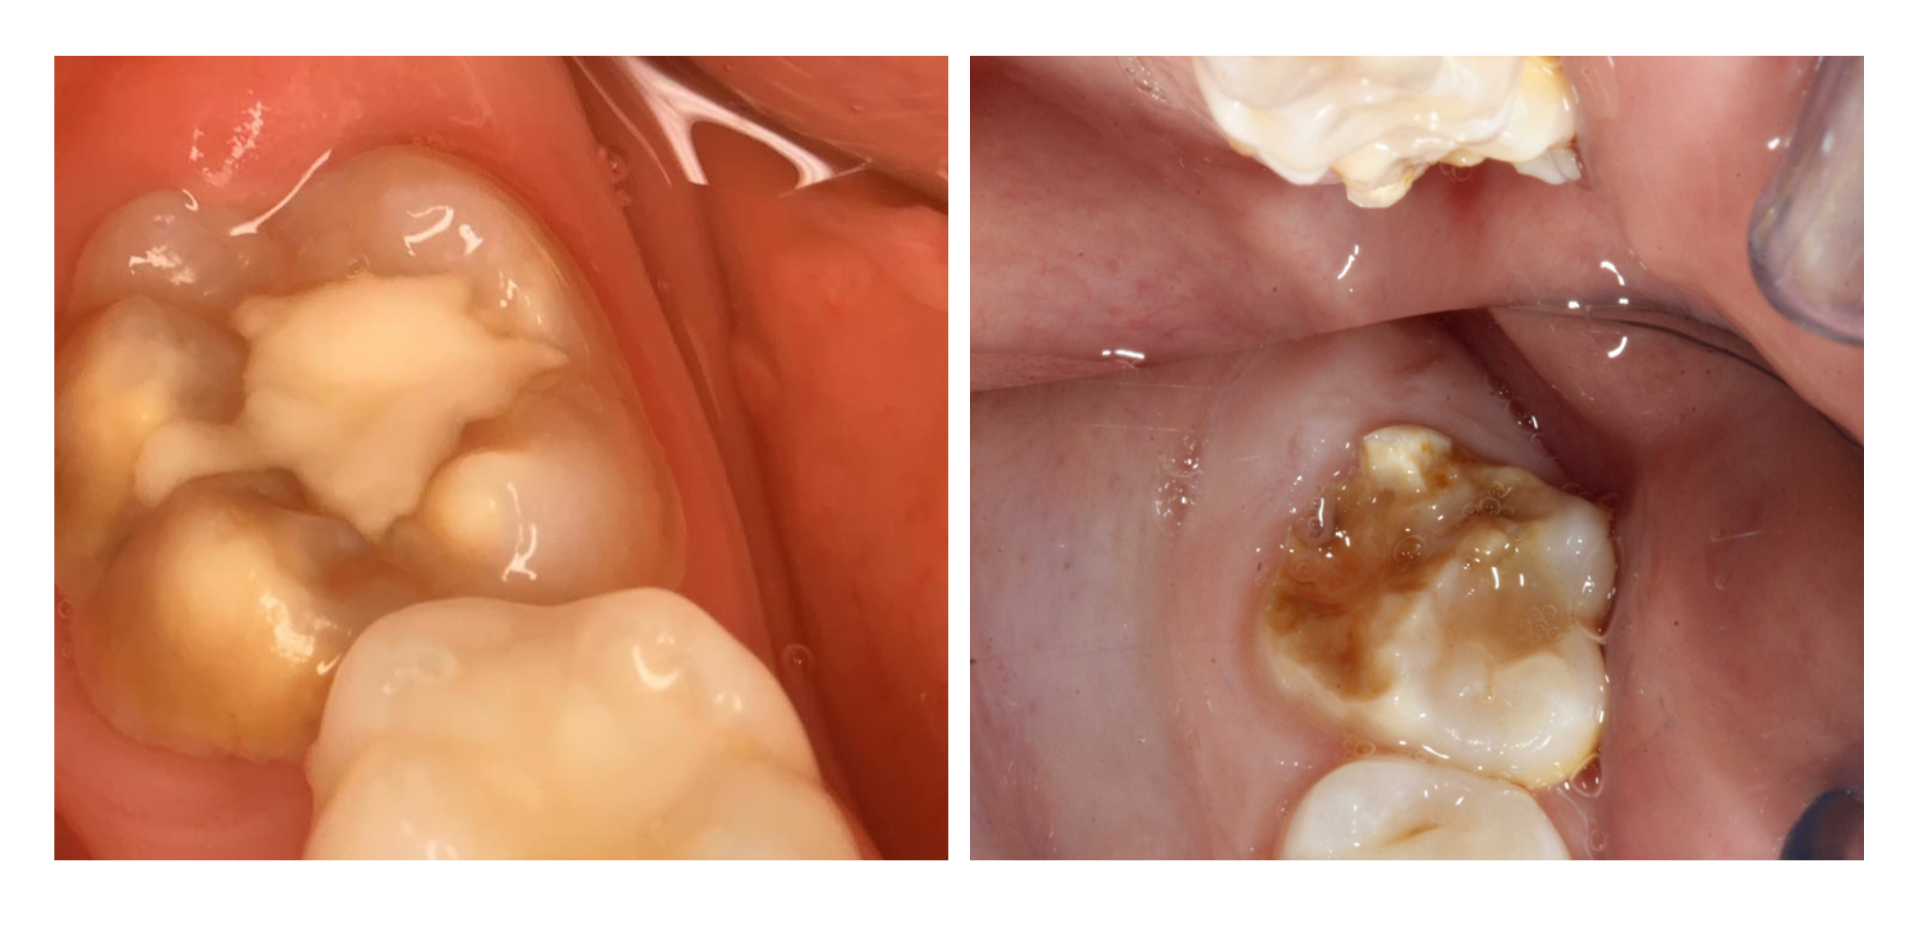

La Hipomineralización Molar (HM) representa un reto de manejo clínico para el odontopediatra. Cuando el paciente presenta defectos severos, con frecuencia surge la duda sobre cuál es la mejor forma de tratarlos.

En este curso se aborda el tratamiento del molar con HM con énfasis en mantener la integridad dentaria mediante restauraciones mínimamente invasivas, restauraciones convencionales o incrustaciones, así como el manejo quirúrgico-ortodóntico en casos severos con mal pronóstico.